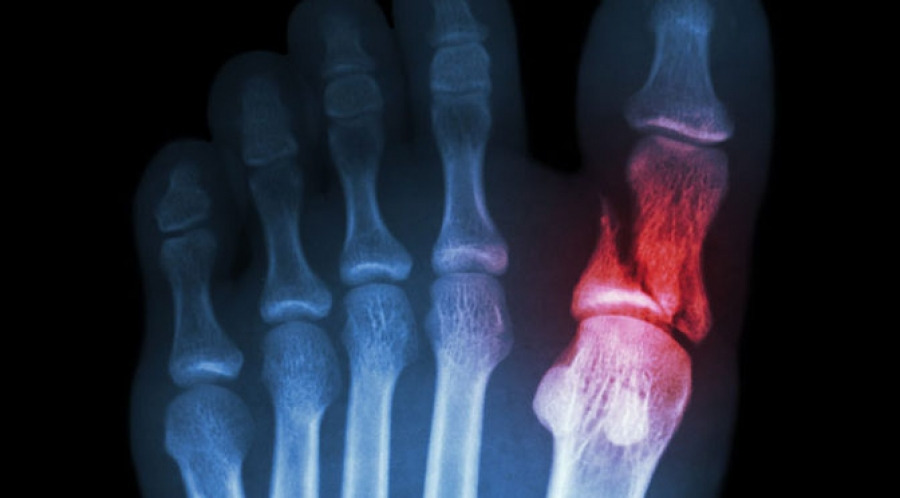

발가락 골절의 기본 이해

발가락 뼈 구조

- 엄지발가락(제1지): 근위·원위 지골 두 개

- 둘째∼넷째 발가락(제2∼4지): 근위·중위·원위 지골 세 개

- 새끼발가락(제5지): 근위·중위·원위 지골 세 개

증상 체크리스트

- 국소 부종·멍·감각저하

- 걷거나 디딜 때 통증이 심해짐

- 발가락 변형(휘어짐·각 변위)

- 피부 아래에서 ‘딸깍’ 소리나 갈라지는 느낌